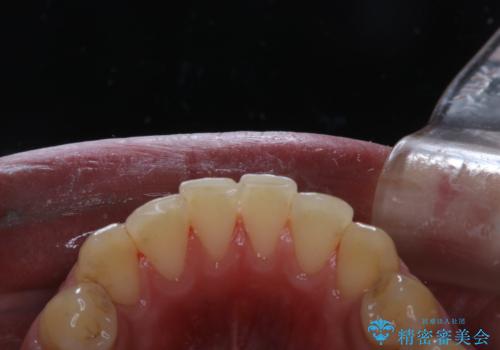

- マスクの着用により、以前より口臭が気になるとのことでした。しっかりと全体的なクリーニングを希望されたため、PMTC60分コースを行いました。

PMTCとはProfessinnal Mechanical Tooth Cleaning・専門器具による歯の機械的な清掃です。

バイオフィルム(細菌の塊)を破壊し、歯の表面をツルツルにすることでお口の中の細菌数を減らし歯周病のリスクが定着するのを防ぎます。更に、歯に新しい汚れがつきにくい状態になります。

バイオフィルムが除去されると、ご自身本来の歯の表面になります。PMTCをすることで口臭予防にもなり、定期的に行うことが大切です。